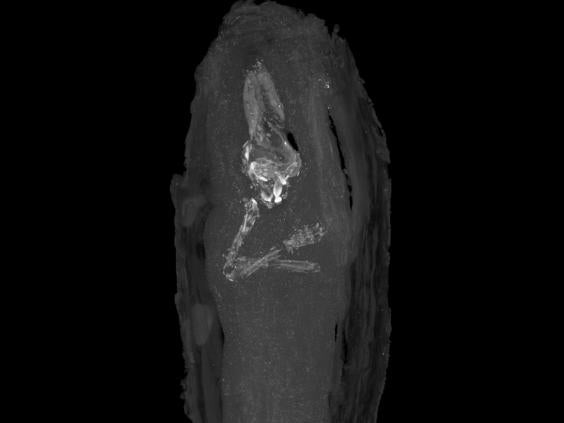

However, the experts decided to try to find out for sure. An X-ray proved inconclusive so it was then decided to use a micro CT scan.

“The cross-sectional images this produced gave the first pictures of the remains of a tiny human body held within the wrappings, which remain undisturbed,” the museum said.

“From the micro CT scan it is noticeable that the foetus has its arms crossed over its chest. This, coupled with the intricacy of the tiny coffin and its decoration, are clear indications of the importance and time given to this burial in Egyptian society.”

The skull and pelvis had collapsed, but the fingers and toes and the long bones of the legs and arms could all be seen.